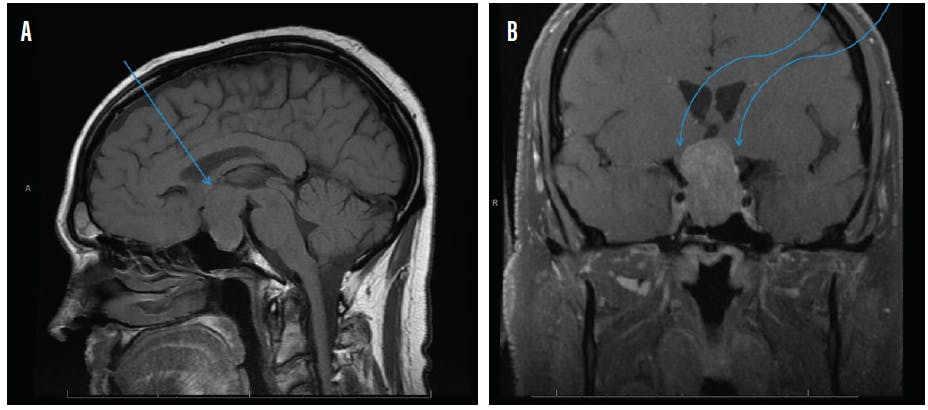

MRI with and without contrast of the brain and/or orbits with attention to the sella is the recommended medium for diagnosis (Figure 2). A patient with a confirmed pituitary macroadenoma should be referred to both neurosurgery and endocrinology. Asymptomatic patients with incidental macroadenomas should receive continued ophthalmologic surveillance because any new visual symptoms strongly indicate a need for surgical intervention. Although there are no established guidelines for the length of ophthalmologic follow-up, lesion size and a progression of visual field defects should inform decisions regarding timeline.

Figure 2. Sagittal midline precontrast T1-weighted MRI showing enlargement of the sella turcica and superior extension of a pituitary macroadenoma (arrow, A). Coronal T1-weighted MRI with contrast showing the optic chiasm stretched and compressed over the mass (arrows, B).